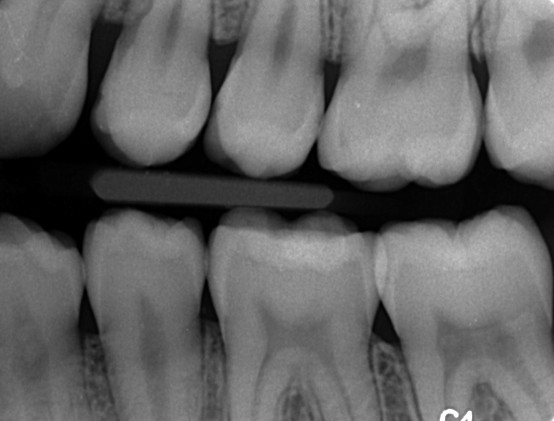

Farvestoffer til afsløring af plak på tænderne. Selv efter tre uger uden tandbørstning er der plakfri områder. Et område uden plak er et cariesfrit område. Med regelmæssig brug af tandbørste og tandtråd er det muligt helt at fjerne cariestruslen. Kun steder hvor plakken ikke fjernes regelmæssigt kan der opstå caries. I naturen er det den grove kost der fjerner plakken. Glatte tandoverflader er en evolutionær genistreg, der letter plakfjernelsen på de flader der udsættes for mindre slid. Formålet med regelmæssig plakfjernelse er at få fjernet plakken fra de tandoverflader, hvor almindelig tygning ikke fjerner plakken (plak-stagnations-områderne). (Else Theilade).